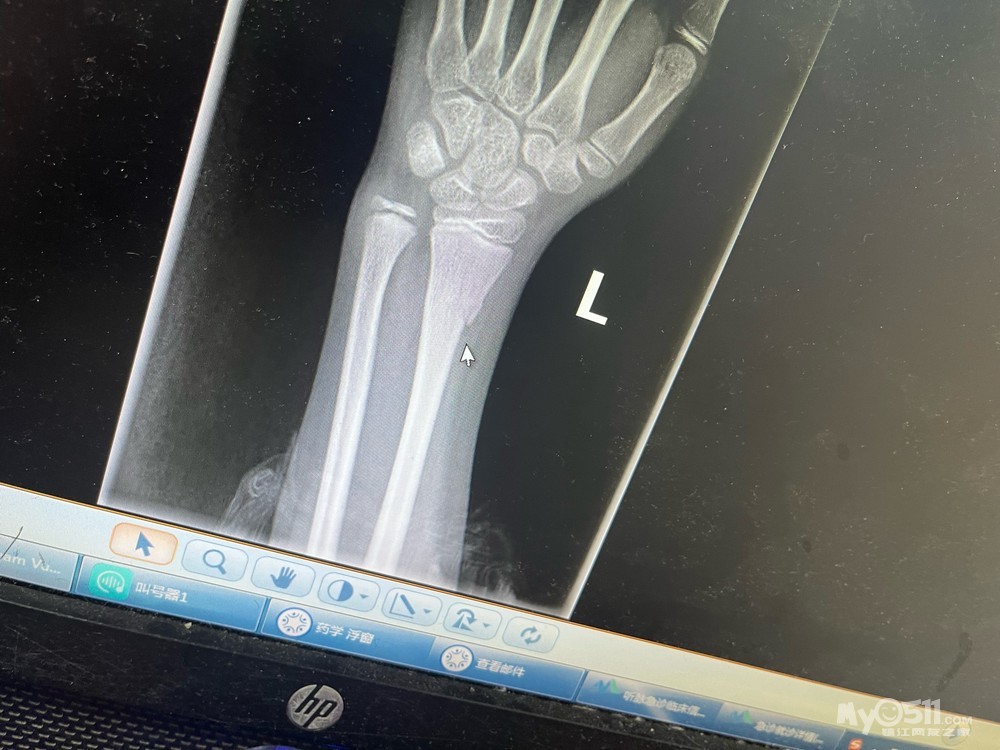

昨天5.18日夜里20:40左右,一家三口由南向北骑行于九华山路与南徐大道路口交汇处镇江市交通运输局附近时,由于慢车道与人行道道路路牙设置高度不合理加上灯光昏暗,导致年满12周岁孩子骑车摔倒导致手臂骨折